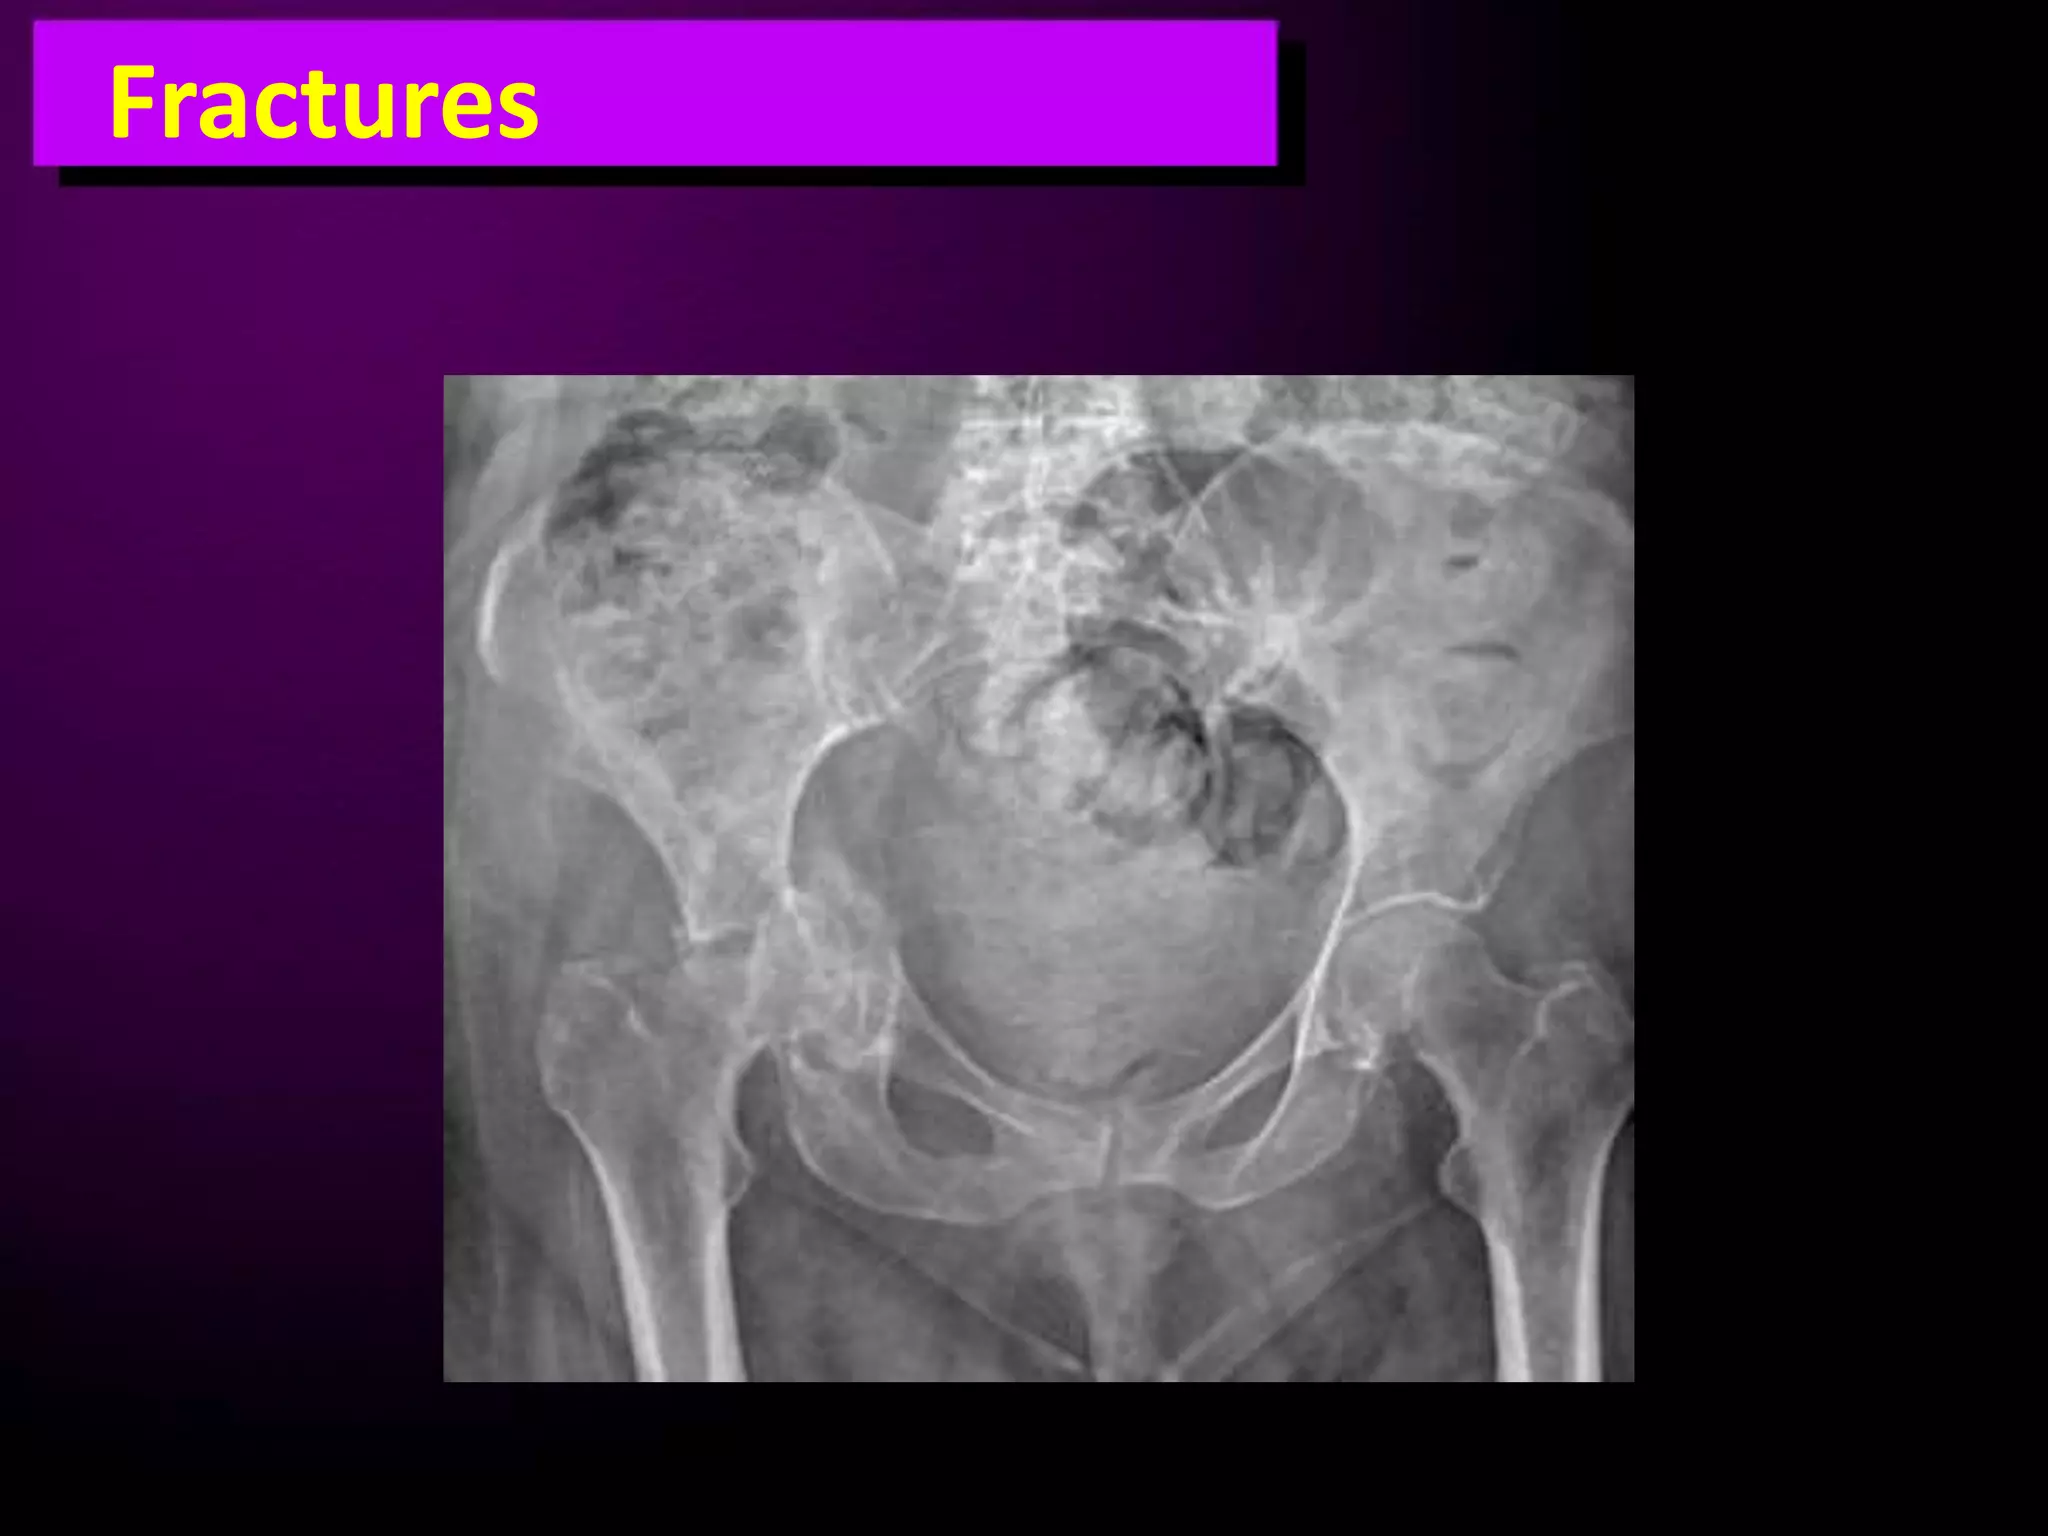

This document discusses trauma to the pelvis, hips, knees, ankles, and feet. It covers anatomy, imaging techniques, and types of fractures and dislocations that can occur in these areas. The types of fractures discussed include pelvic ring fractures, acetabular fractures, and fractures of the femur, tibia, fibula, and bones of the foot. Imaging views used include AP, inlet, and outlet views of the pelvis. Dislocations and fractures of the knee, ankle, and foot joints are also examined.